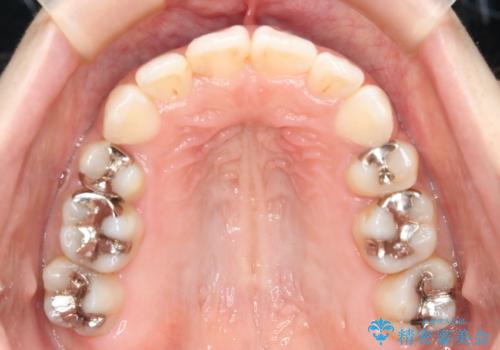

- 歯のガタつきと出っ歯が気になるので矯正治療を希望し来院された患者様です。

上下顎とも歯を並べられるスペースが無く、口元を下げたいというご希望だったので、抜歯とワイヤー矯正を併用した治療を計画しました。

抜歯スペースを利用し口元を大きく下げることが出来ました。